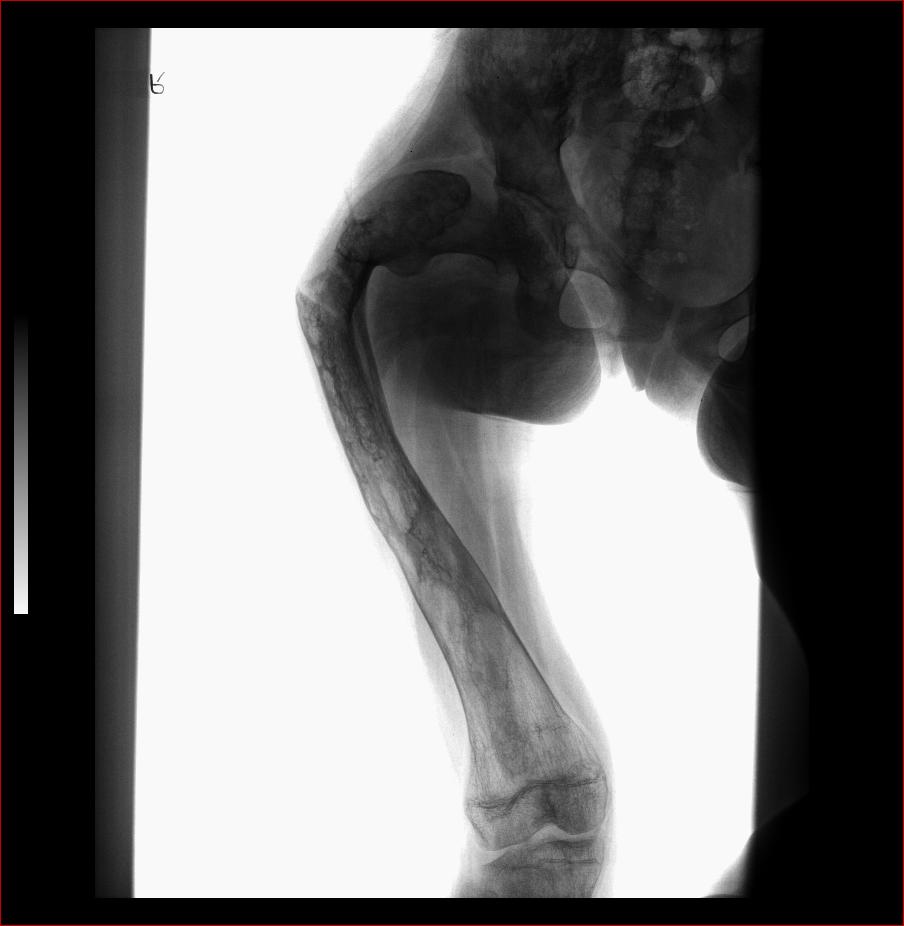

标题: X3602:F17Y,右腿畸形 [打印本页]

标题: X3602:F17Y,右腿畸形

股骨藏刀样畸形改变,骨髓腔消失,骨皮质结构紊乱,典型的骨纤维异常增殖症。

股骨骨纤维异常增殖症并畸形、病理性骨折。

股骨骨纤维异常增殖症并病理性骨折。

考虑股骨骨纤维异常增殖症并病理性骨折。